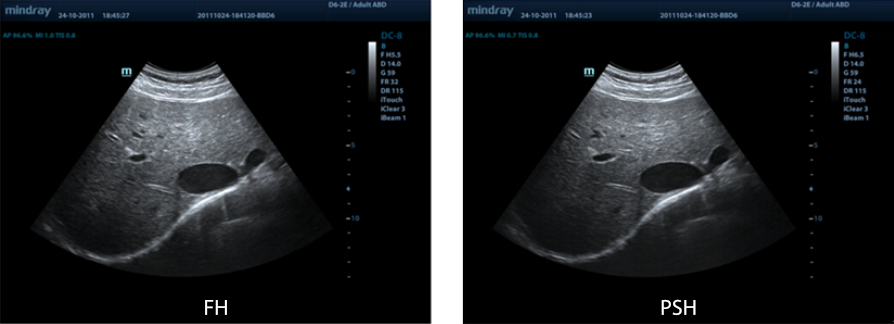

PSHI? (Imagen armónica con inversión de fase)

Las imágenes armónicas puras permiten suprimir los artefactos, generando menos ruido y aumentando la calidad de las imágenes gracias a una mejor resolución de contraste.